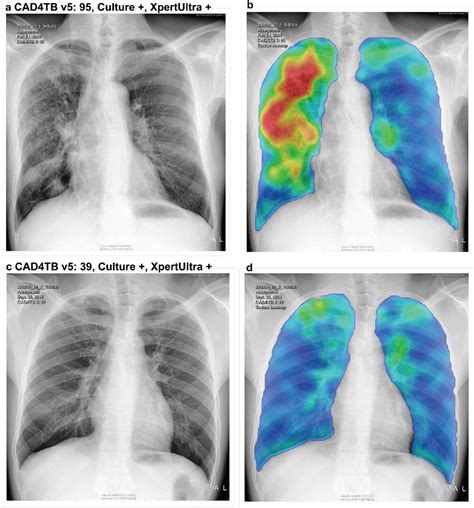

• Chest X-ray

Diagnosis Tuberculin skin test, IGRA, chest X-ray, sputum test, biopsy Chest X-ray, blood tests, sputum test, pulse oximetry, CT scan